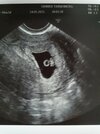

Ja już po wizycie;) wszystko ładnie i dobrze;) moj gin polecił mi 3 innych ginekologów, którzy lepiej się mną zajmą w ciąży. Także będę się na dniach umawiać na wizyte;)

Załączniki

• 20210524_204943.jpg

20210524_204943.jpg

1,5 MB · Wyświetleń: 132